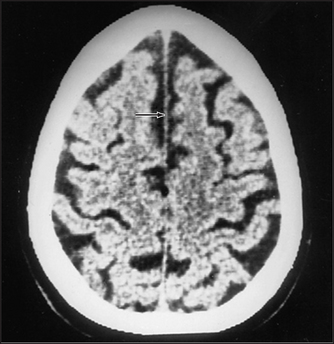

Figure 36.7 Cerebral atrophy In this CT scan, note the expanded sulci, the shrunken gyri and the retraction of the cerebral cortex from the inner table of the skull. The ventricles have expanded. (Kaufman D. Clinical neurology for psychiatrists, 6th edn. Saunders, 2006.)